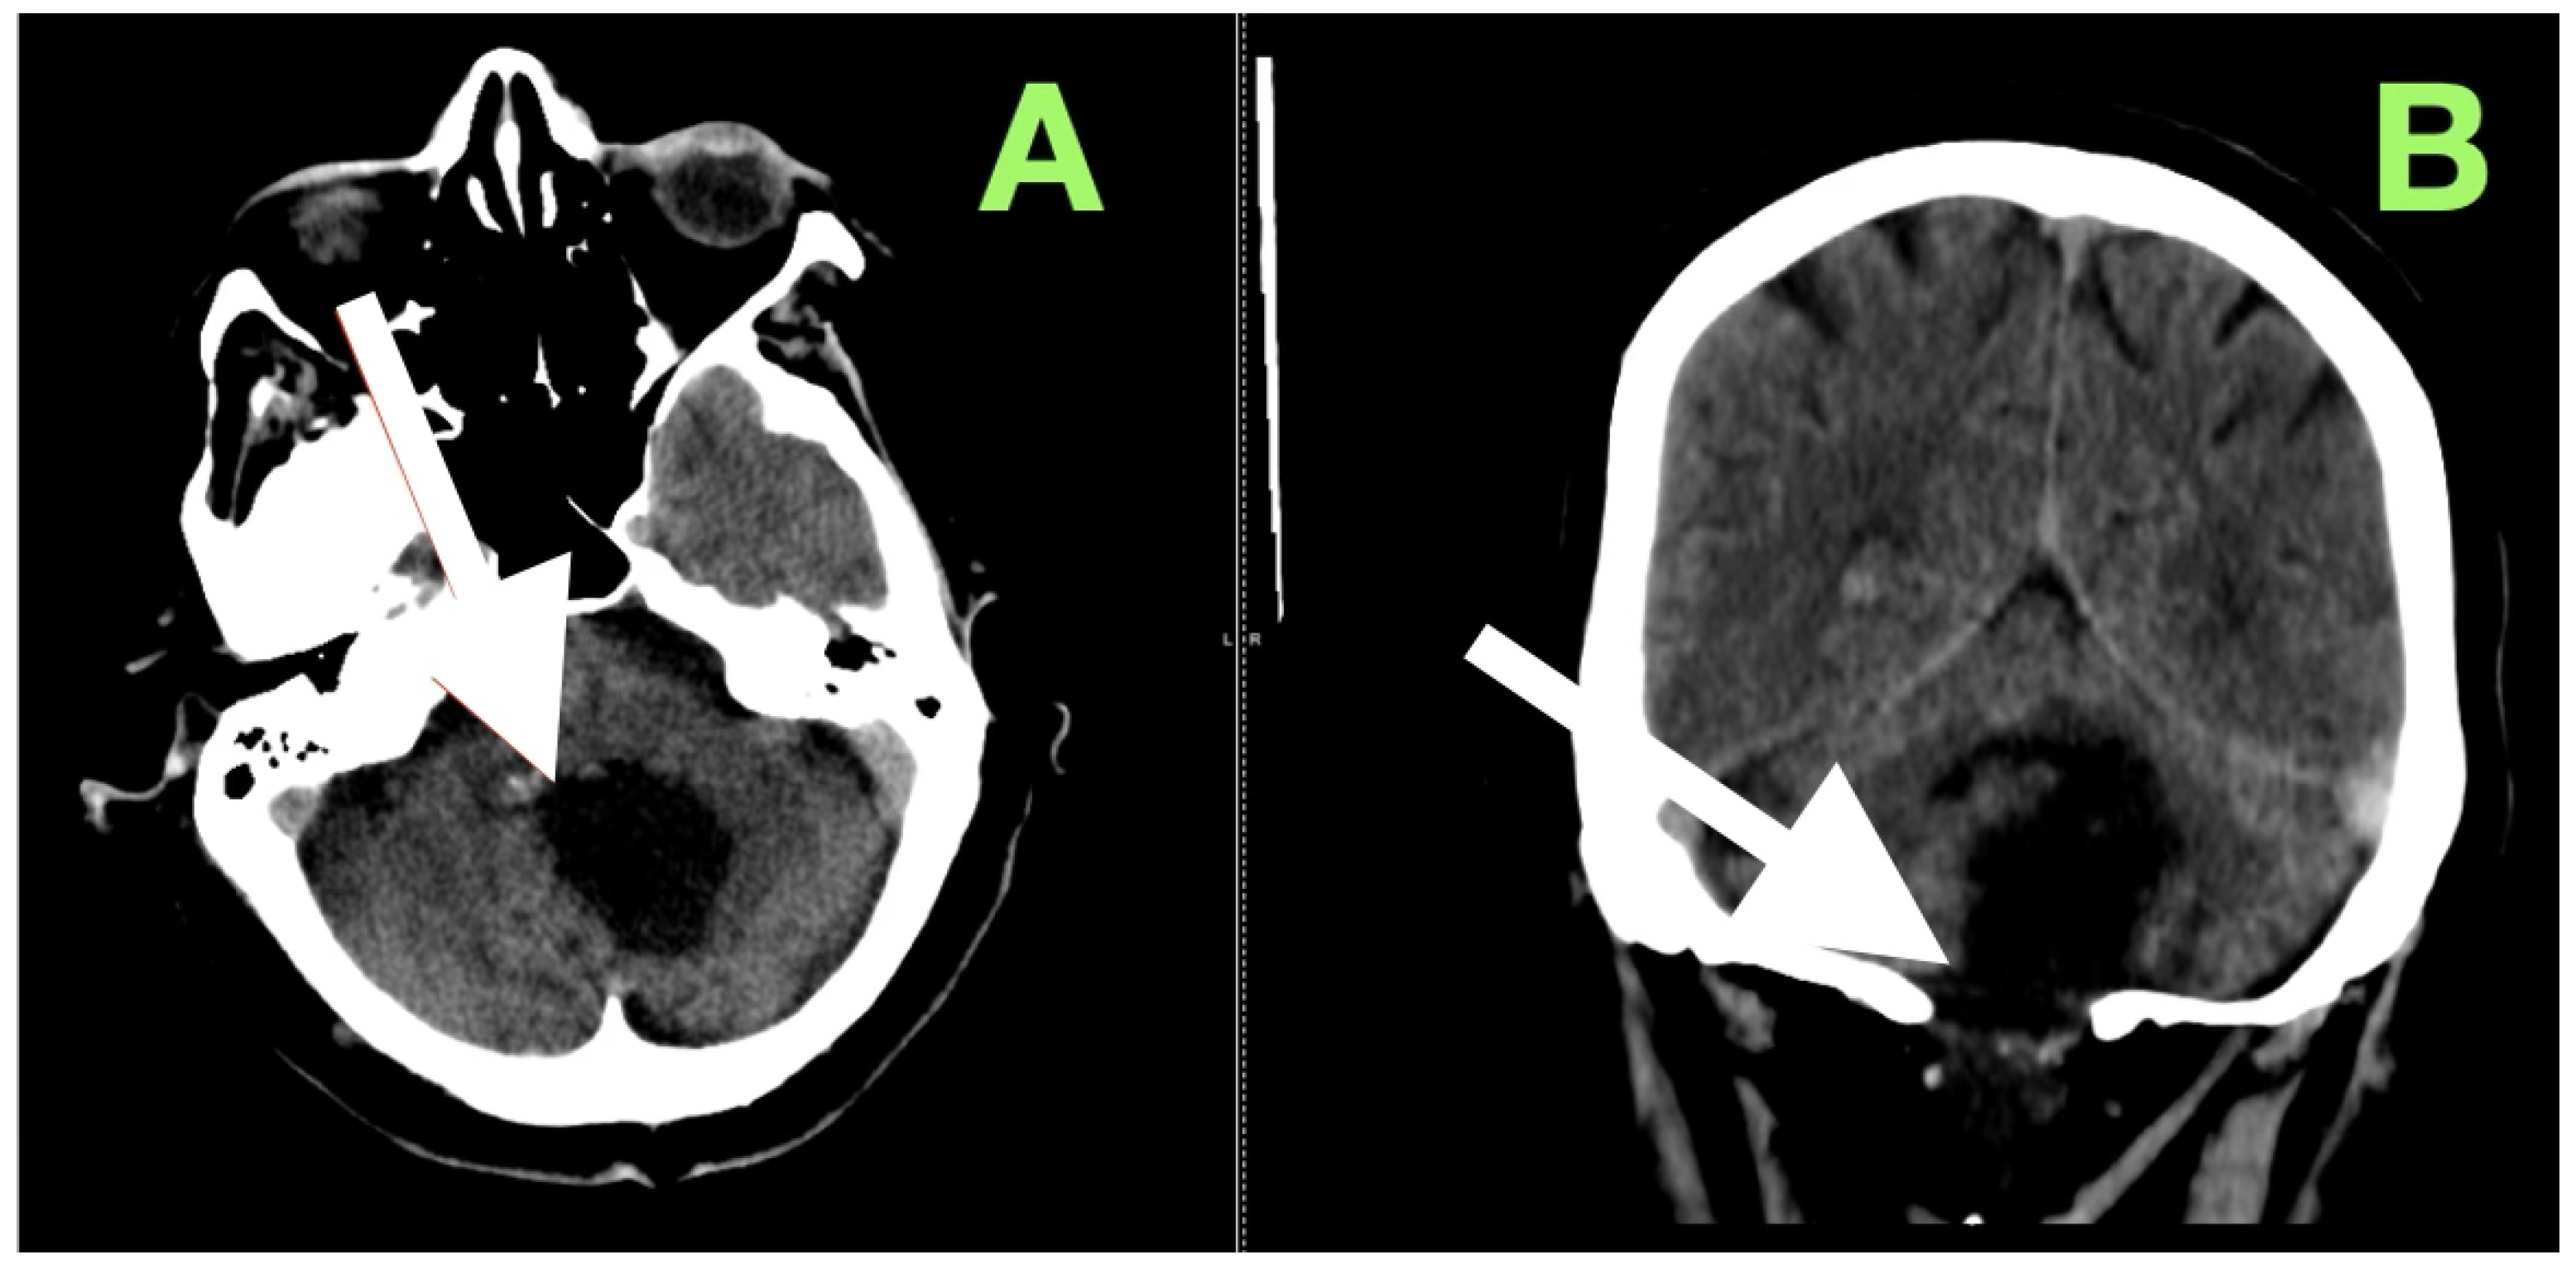

After extubation in the neurosurgical ICU postoperatively, early recovery included trunk stability, improved gaze-holding nystagmus, and less dysmetria. There were no cranial nerve impairments noted, and swallowing remained safe. Postoperative CT (Figure 3) confirmed complete decompression and re-expansion of the fourth ventricle, patency the cerebellomedullary cistern, symmetric cerebellar hemispheres, and patent foramen of Magendie. There was no presence of hemorrhage, infarction or hydrocephalus, and the operative cavity duplicated the original tumor size, underscoring the painstaking extra-axial dissection while maintaining parenchymal margins.

Figure 3. Immediate postoperative non-contrast CT scan demonstrating complete removal of the fourth-ventricular epidermoid tumor and restoration of posterior fossa anatomy. (A) Axial view shows a well-defined postoperative cavity in the midline vermian and fourth-ventricular region, with full re-expansion of the fourth ventricle and reappearance of the cerebellomedullary cistern. The brainstem contour is normalized, and no residual mass effect or obstructive hydrocephalus is present. (B) Coronal reconstruction confirms symmetrical cerebellar hemispheres, midline restoration of the fourth ventricle, and patent foramen of Magendie, with no acute hemorrhage or postoperative edema. The surgical cavity follows the anatomical boundaries of the preoperative lesion, reflecting precise extra-axial microsurgical dissection and preservation of surrounding neural tissue.